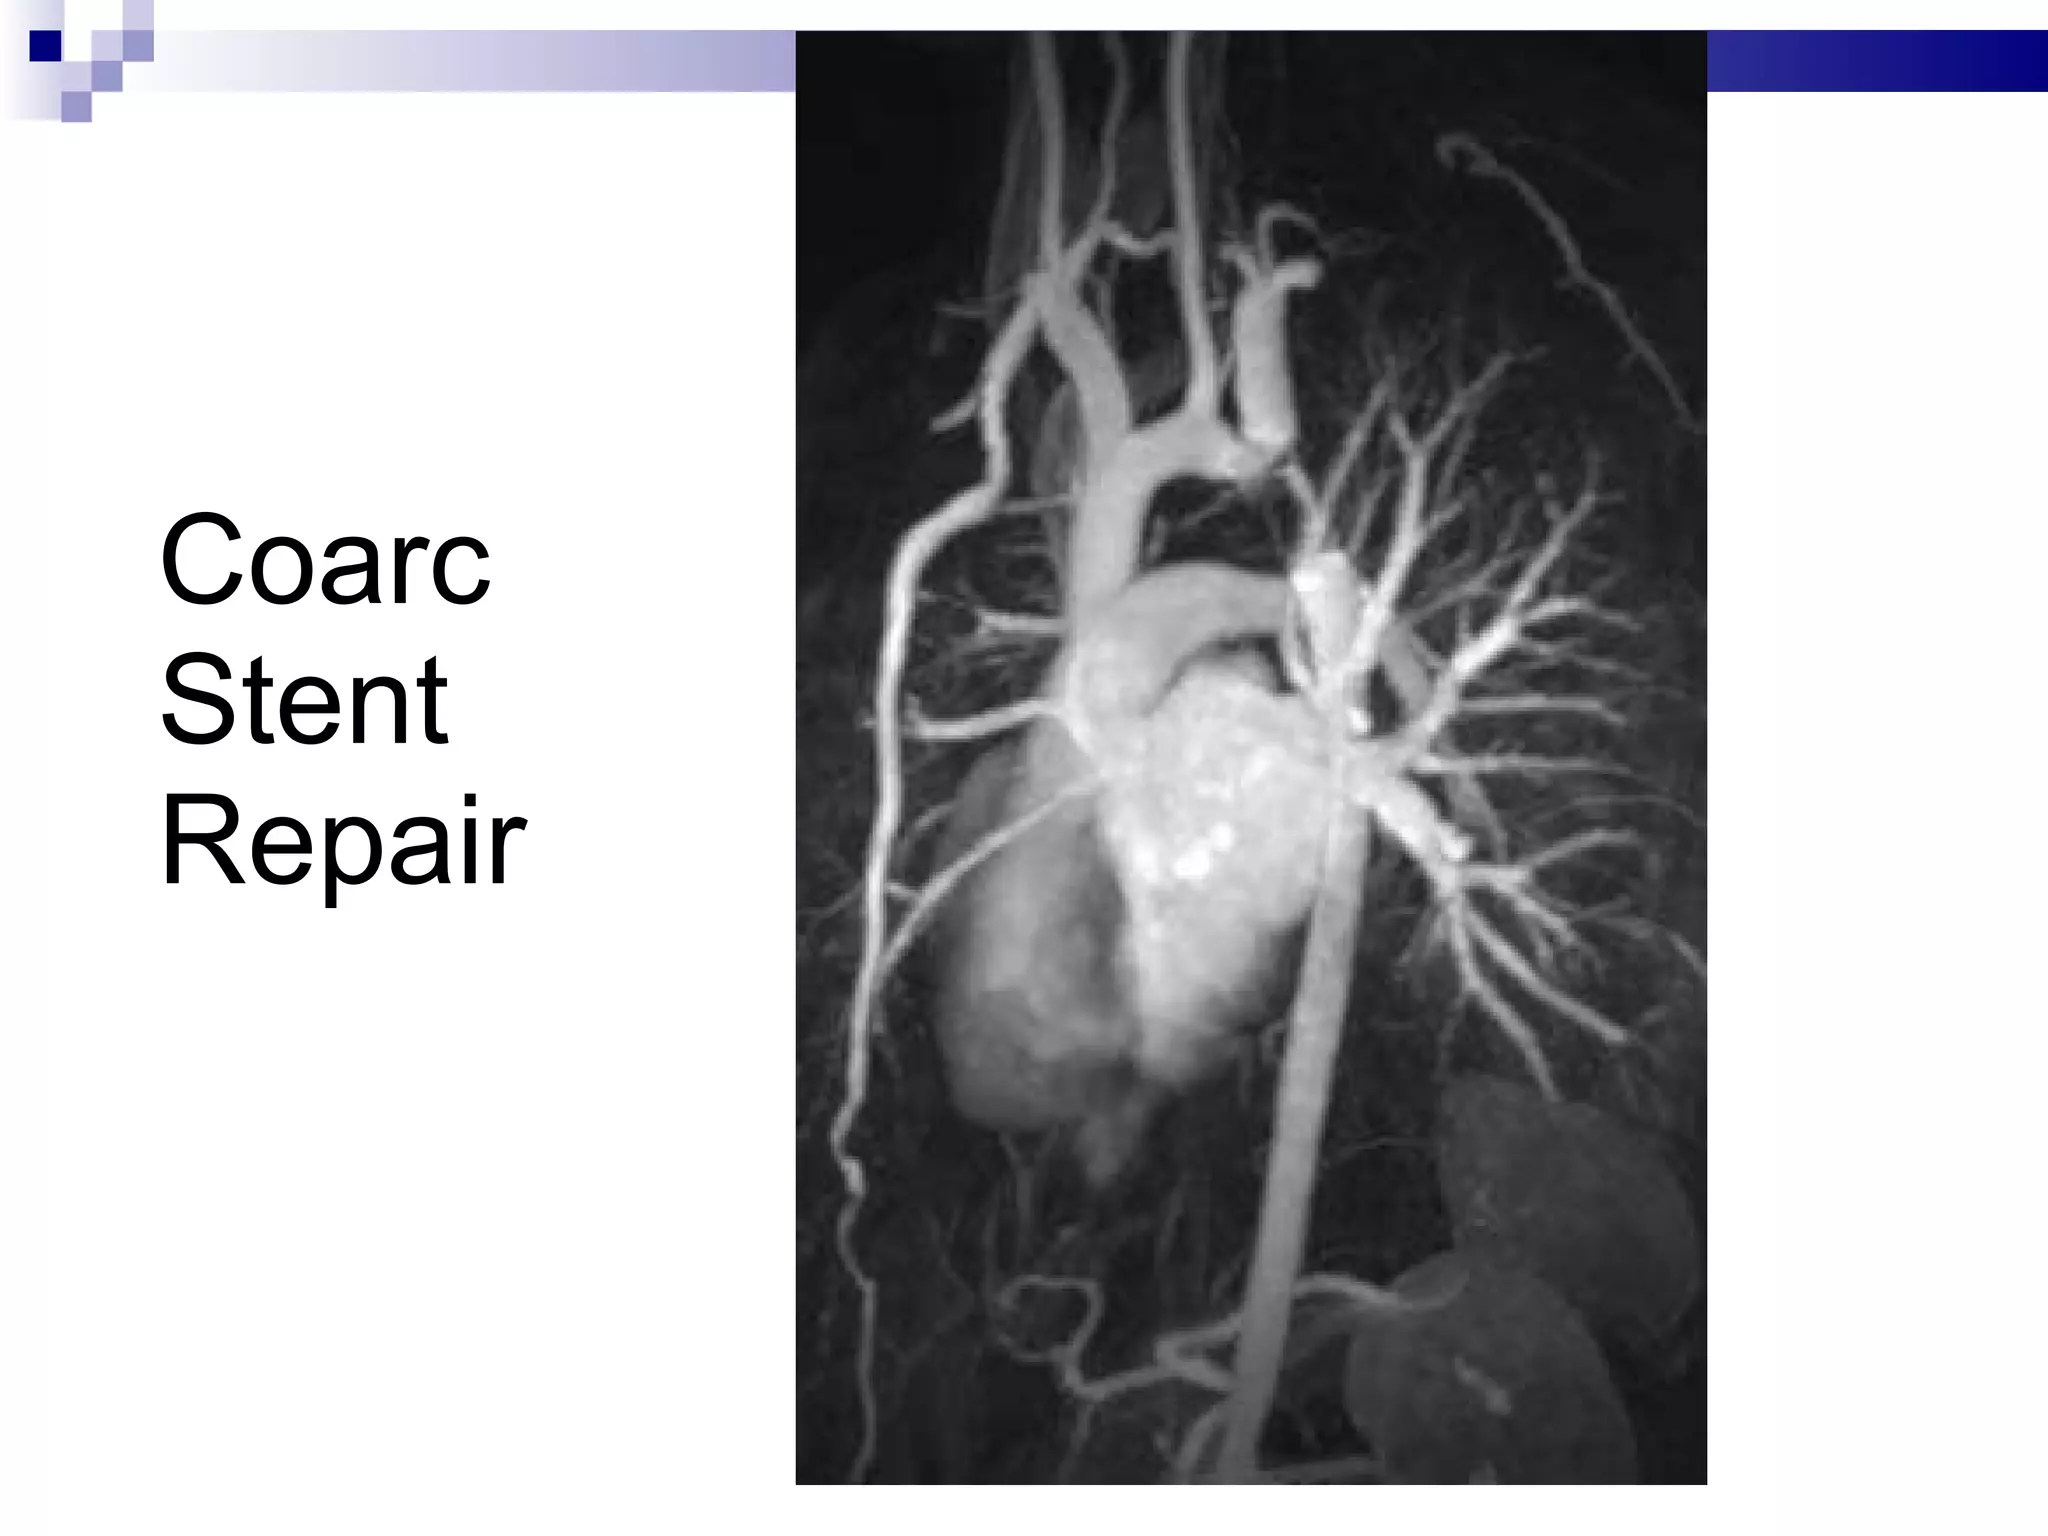

Coarc Stent Repair